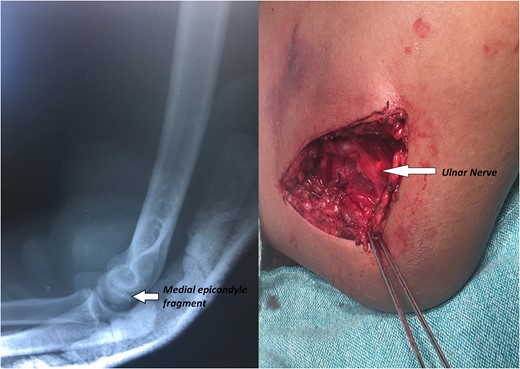

A 14-year-old male patient presented to the emergencies department complaining of intense pain in the left elbow secondary to a fall with an outstretched hand while practicing soccer. He had no significant comorbidities. At physical examination he presented with deformity located on the left elbow, he was unable to passively or actively mobilize it, he reported paresthesias and diminished sensation located on the fifth and fourth digit. X-rays showed a dislocation on the left elbow and an avulsive fracture of the medial epicondyle of the distal humerus (Fig. 1). He was taken to the operating room where a closed manipulation was performed; however the reduction was not achieved due to the interposition of the fractured medial epicondyle. A medial approach to the elbow was performed; intra-operative findings included rupture of the medial capsule and intra-articular interposition of the fragment of the medial epicondyle with a posterolateral dislocation of the elbow, the ulnar nerve showed compressive injuries at the site of the fracture (Fig. 2). Extraction and fixation of the interposed intra-articular fragment was performed followed by elbow reduction and a medial capsule repair, without ulnar nerve transposition (Fig. 3). The patient was left with a posterior splint for a month. After a 3 month follow-up, he has recovered full range of motion of the elbow with recovery of strength and sensation over the distribution of the ulnar nerve.

X-rays showing the result of the first attempt of closed manipulation and open reduction.

There is no general agreement in the literature whether or not to perform an ulnar decompression and transposition. In this case, we considered that the ulnar neuropraxia was produced by the pressure of the bony structures of the elbow over the nerve and considered that the injury would resolve after reduction and fracture fixation. Disadvantages associated to ulnar decompression and transposition include: larger incision and operative time, higher risk of neuritis due to implant irritation [6, 10].